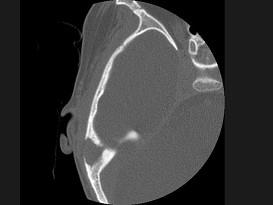

女性,17岁,右耳乳突区隐痛,右耳后乳突区出现包块,逐渐增大,CT检查如图所示,请选择最可能的 ( )